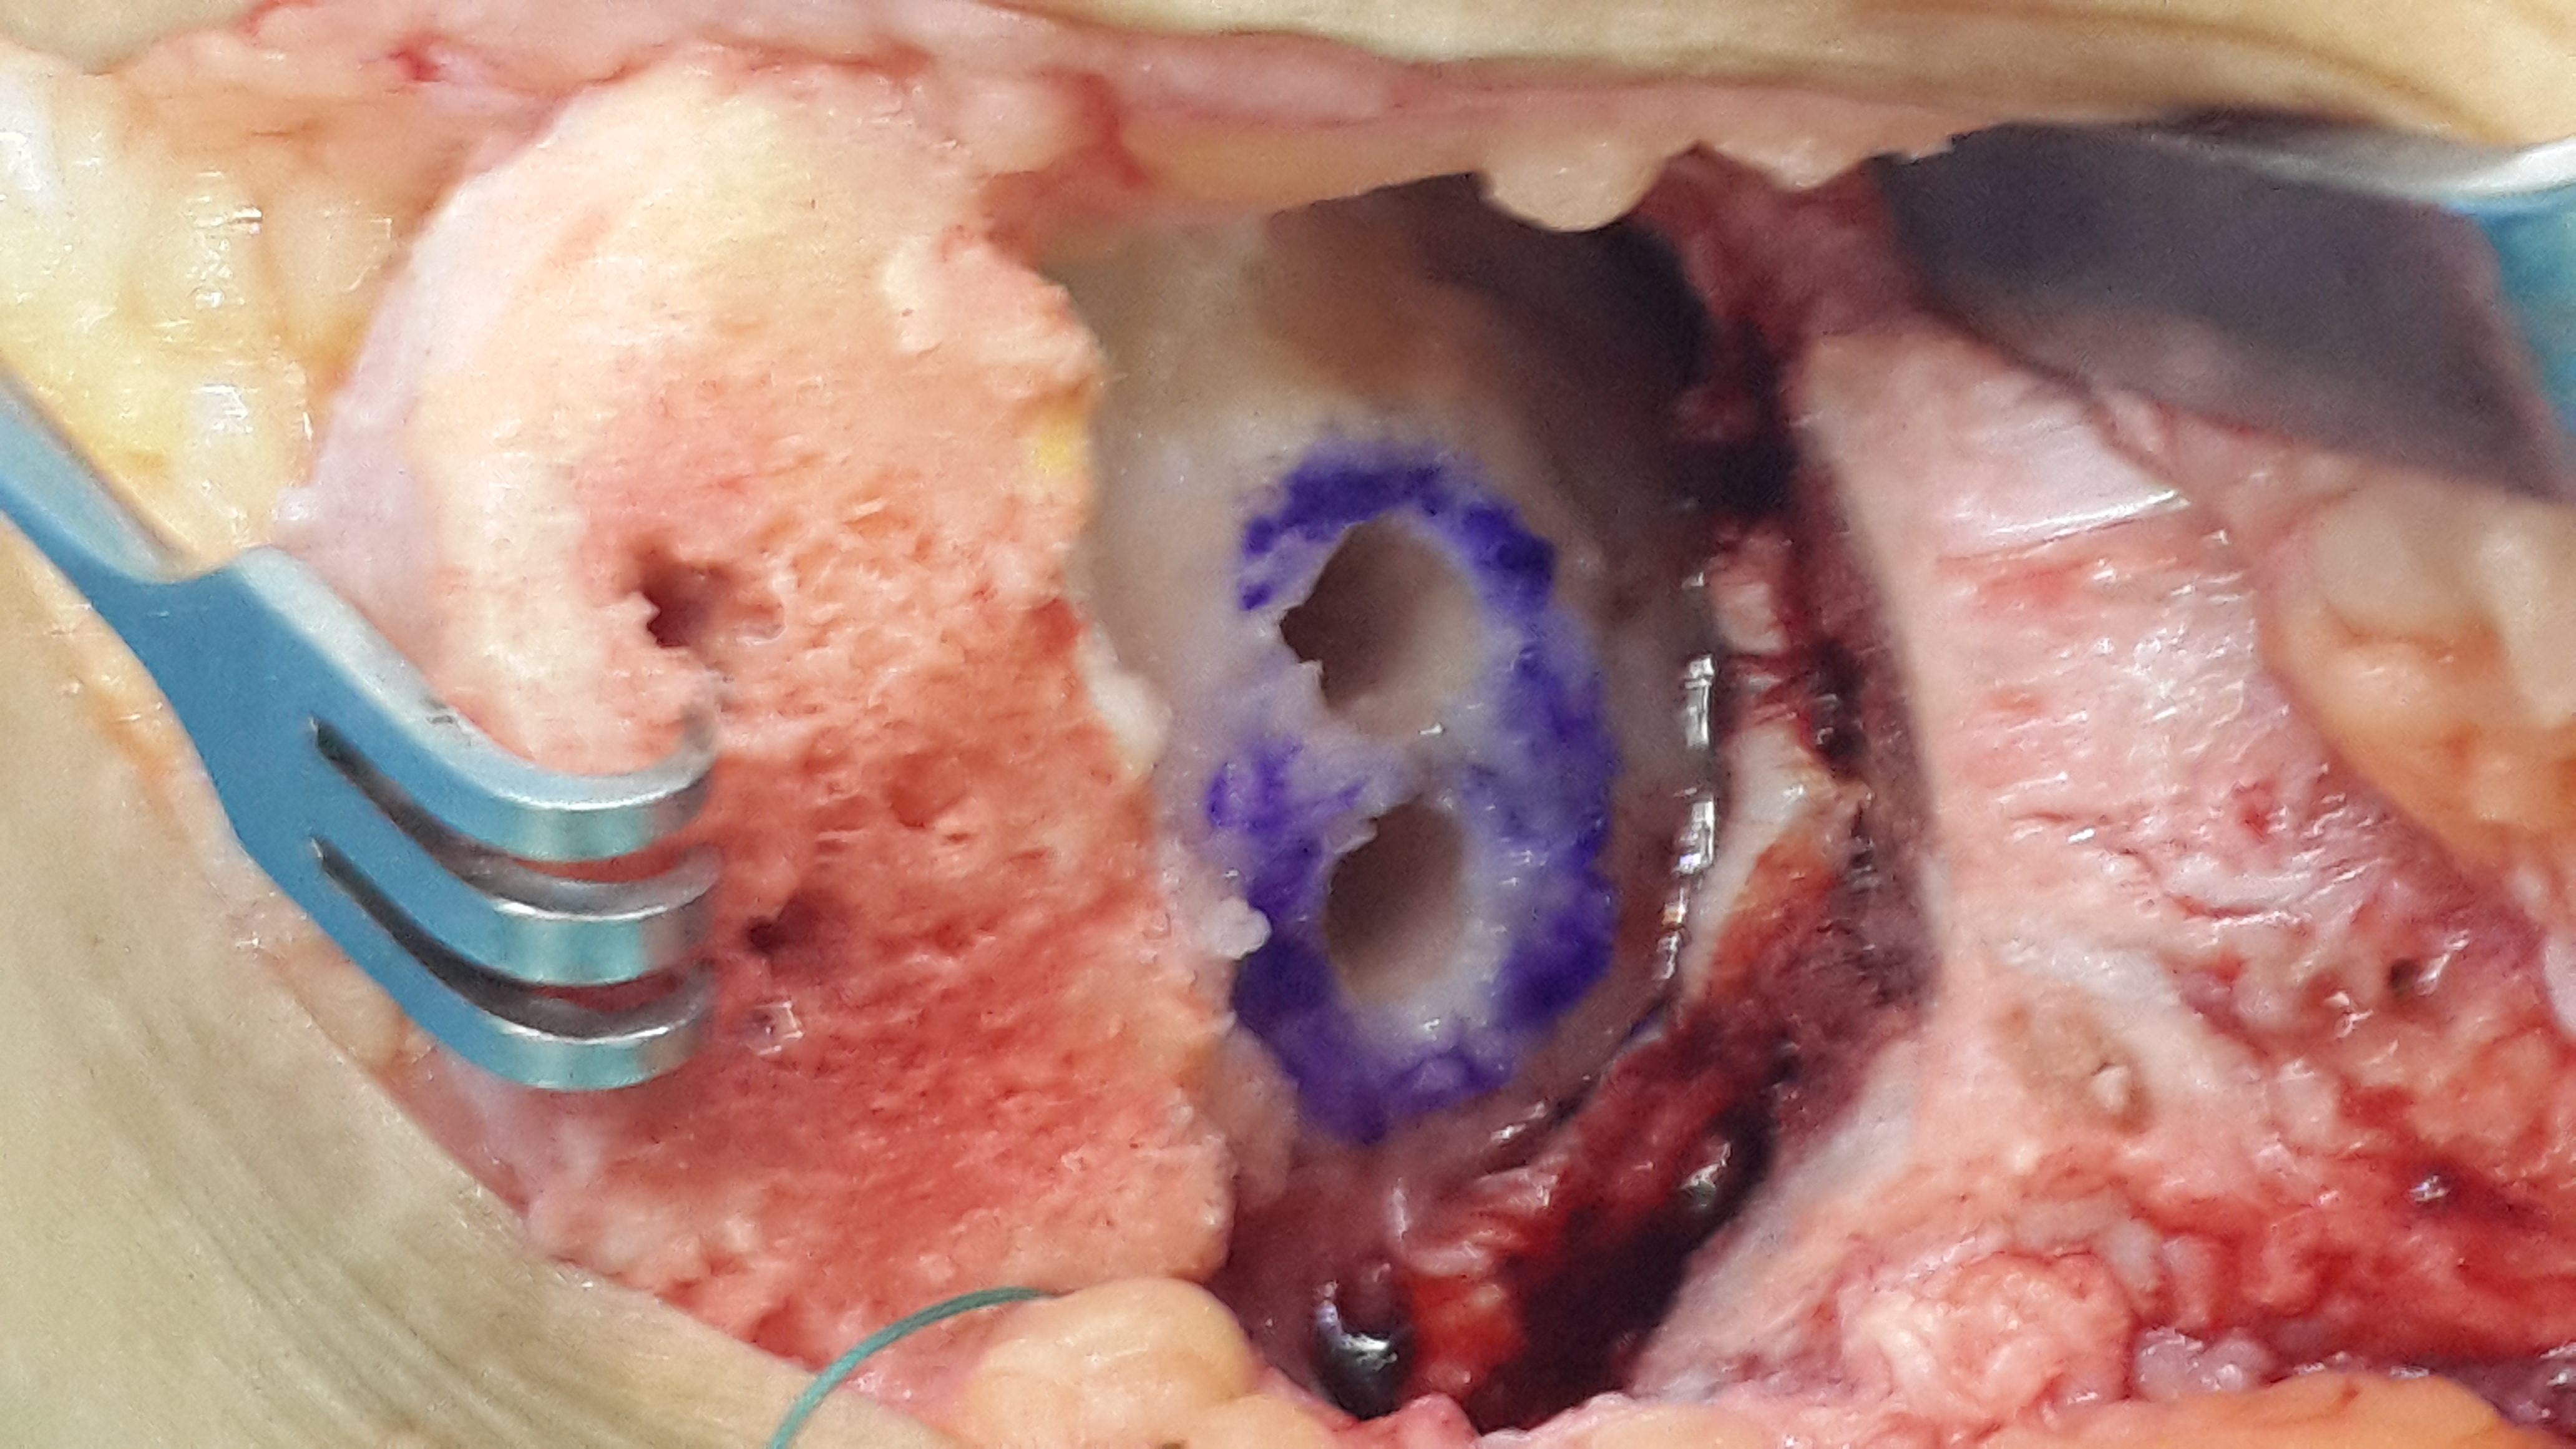

11 Şub Ayak bileği kıkırdak transferi by admin in AYAK - AYAK BİLEĞİ CERRAHİSİ VAKA ÖRNEKLERİComments